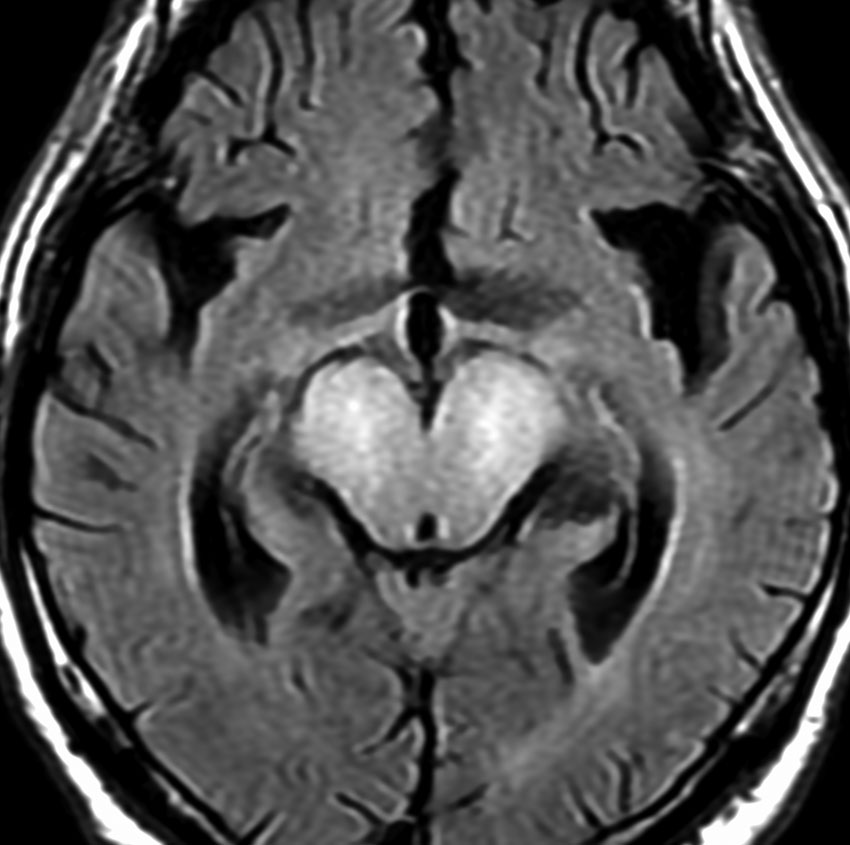

MRI画像所見 60代で嚥下障害と構音障害で発症した例

延髄から中脳まで腫瘍があって脳幹部が腫れています。この画像ですと,小児のびまん性橋膠腫(DIPG,びまん性正中グリオーマ)のように見えます

両側視床から大脳基底核,両側大脳半球深部白質,脳梁まで広範囲に腫瘍が存在します。退形成性星細胞腫のようにまだらにガドリニウム増強されます。